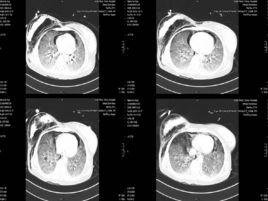

濕性羅音(又稱水泡音),呼吸時,氣流通過含有稀薄的分泌物的氣管或支氣管時,使分泌物形成水泡並迅速爆破而產生的聲音。它是吸氣時氣體通過呼吸道內的稀薄分泌物而產生的聲音,按呼吸道腔徑大小及分泌物多少水泡音有大、中、小之分(或稱粗、中、細濕羅音),分別產生於大、中、小支氣管內。大水泡音,音強而調低;小水泡音,音弱而調高;中水泡音介於二者之間。小水泡音,最細者猶如捻發時所產生的聲音,稱為捻發音。 大水泡音多見於支氣管擴張、肺結核空洞、肺水腫及昏迷等患者;中、小水泡音見於支氣管肺炎、慢性支氣管炎、肺間質纖維化等。 濕性羅音聽診特點呈間斷性、短暫,位置比較固定,常在吸氣末時更明顯,咳嗽後減輕或消失。

濕性羅音可以瀰漫於全肺,也可以局限於肺的某一部位,吸氣與呼氣時均可聽到,但以深吸氣時更為明顯。臨床常見於支氣管炎、肺炎、肺結核、肺淤血、肺水腫及支氣管擴張。